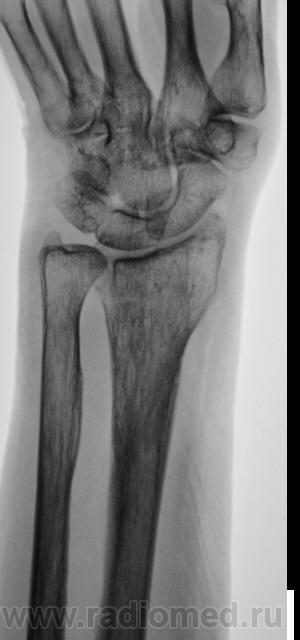

Травма.   Пациент направлен на рентгенографию лучезапястного сустава.

СЛУЧАЙ № 2.